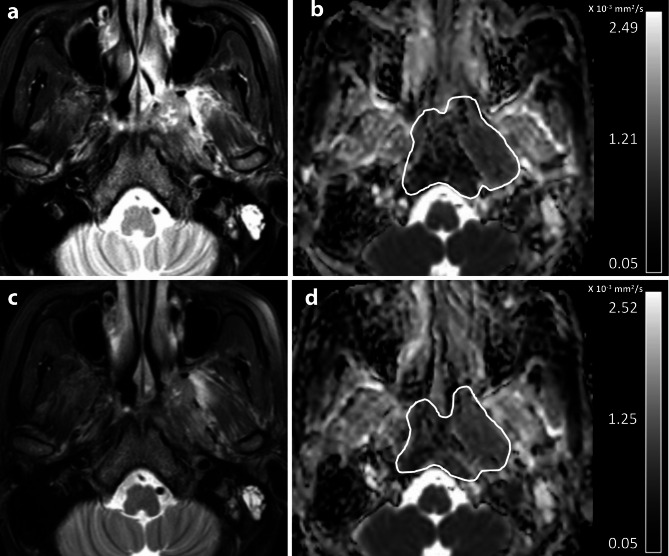

Purpose: To investigate change in diffusion weighted imaging (DWI) between pre-treatment (pre-) and after induction chemotherapy (post-IC) for long-term outcome prediction in advanced nasopharyngeal carcinoma (adNPC).

Materials and methods: Mean apparent diffusion coefficients (ADCs) of two DWIs (ADCpre and ADCpost-IC) and changes in ADC between two scans (ΔADC%) were calculated from 64 eligible patients with adNPC and correlated with disease free survival (DFS), locoregional recurrence free survival (LRRFS), distant metastases free survival (DMFS), and overall survival (OS) using Cox regression analysis. C-indexes of the independent parameters for outcome were compared with that of RECIST response groups. Survival rates between two patient groups were evaluated and compared.

Results: Univariable analysis showed that high ΔADC% predicted good DFS, LRRFS, and DMFS p < 0.05), but did not predict OS (p = 0.40). Neither ADCpre nor ADCpost-IC (p = 0.07 to 0.97) predicted outcome. Multivariate analysis showed that ΔADC% independently predicted DFS, LRRFS, and DMFS (p < 0.01 to 0.03). Compared with the RECIST groups, the ΔADC% groups (threshold of 34.2%) showed a higher c-index for 3-year (0.47 vs. 0.71, p < 0.01) and 5-year DFS (0.51 vs. 0.72, p < 0.01). Compared with patients with ΔADC%<34.2%, patients with ΔADC%≥34.2% had higher 3-year DFS, LRRFS and DMFS of 100%, 100% and 100%, respectively (p < 0.05).

Conclusion: Results suggest that ΔADC% was an independent predictor for long-term outcome and was superior to RECIST guideline for outcome prediction in adNPC. A ΔADC% threshold of ≥ 34.2% may be valuable for selecting patients who respond to treatment for de-escalation of treatment or post-treatment surveillance.